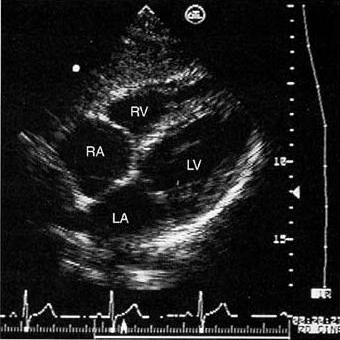

6.心尖四腔切面

(1)正常解剖结构的超声心动图表现: 图像右侧自上向下依次为左心室、二尖瓣、左房,左侧为右心室、二尖瓣、右房,中央为室间隔、房间隔。

心尖四腔切面

(4)正常测值

①左室长径:舒张末期为7.0~8.4cm,收缩末期为5.0~6.4cm 。

②左房内径:上下径为3.1~5.3cm (收缩末期,二尖瓣环联线中点至左房顶部),横径为3.0~5.3cm。(收缩末期,心房中部)。

③右室内径:横径为2.5~4.2cm(舒张末期径),长径为5.8~7.8cm(舒张末期径)。

④右房内径为3.4~4,9cm , 横径为2.9~4,5cm (心尖四腔切面,收缩末期上下径)。

Schematic diagram of the apical four-chamber view

showing the relationships of the left and right ventricles (LV and RV) and atria (LA and RA). In the left ventricle, the papillary muscle, chordae, and anterior and posterior mitral leaflets (AMVL, PMVL) are seen. The descending aorta (DA) is seen in partial cross section lateral to the left atrium, while the right superior pulmonary vein (RSPV) drains into the left atrium adjacent to the interatrial septum. In the right ventricle, the moderator band (MBlack Eye and the anterior and septal tricuspid valve leaflets (ATVL and STVL) are seen. Note the ventriculoatrial septum (VAS) separating the left ventricle from the right atrium in association with the normal, slightly more apical position of the tricuspid compared with the mitral valve annulus.

Two-dimensional echo images in an apical four-chamber view at end-diastole (above) and end-systole (below).